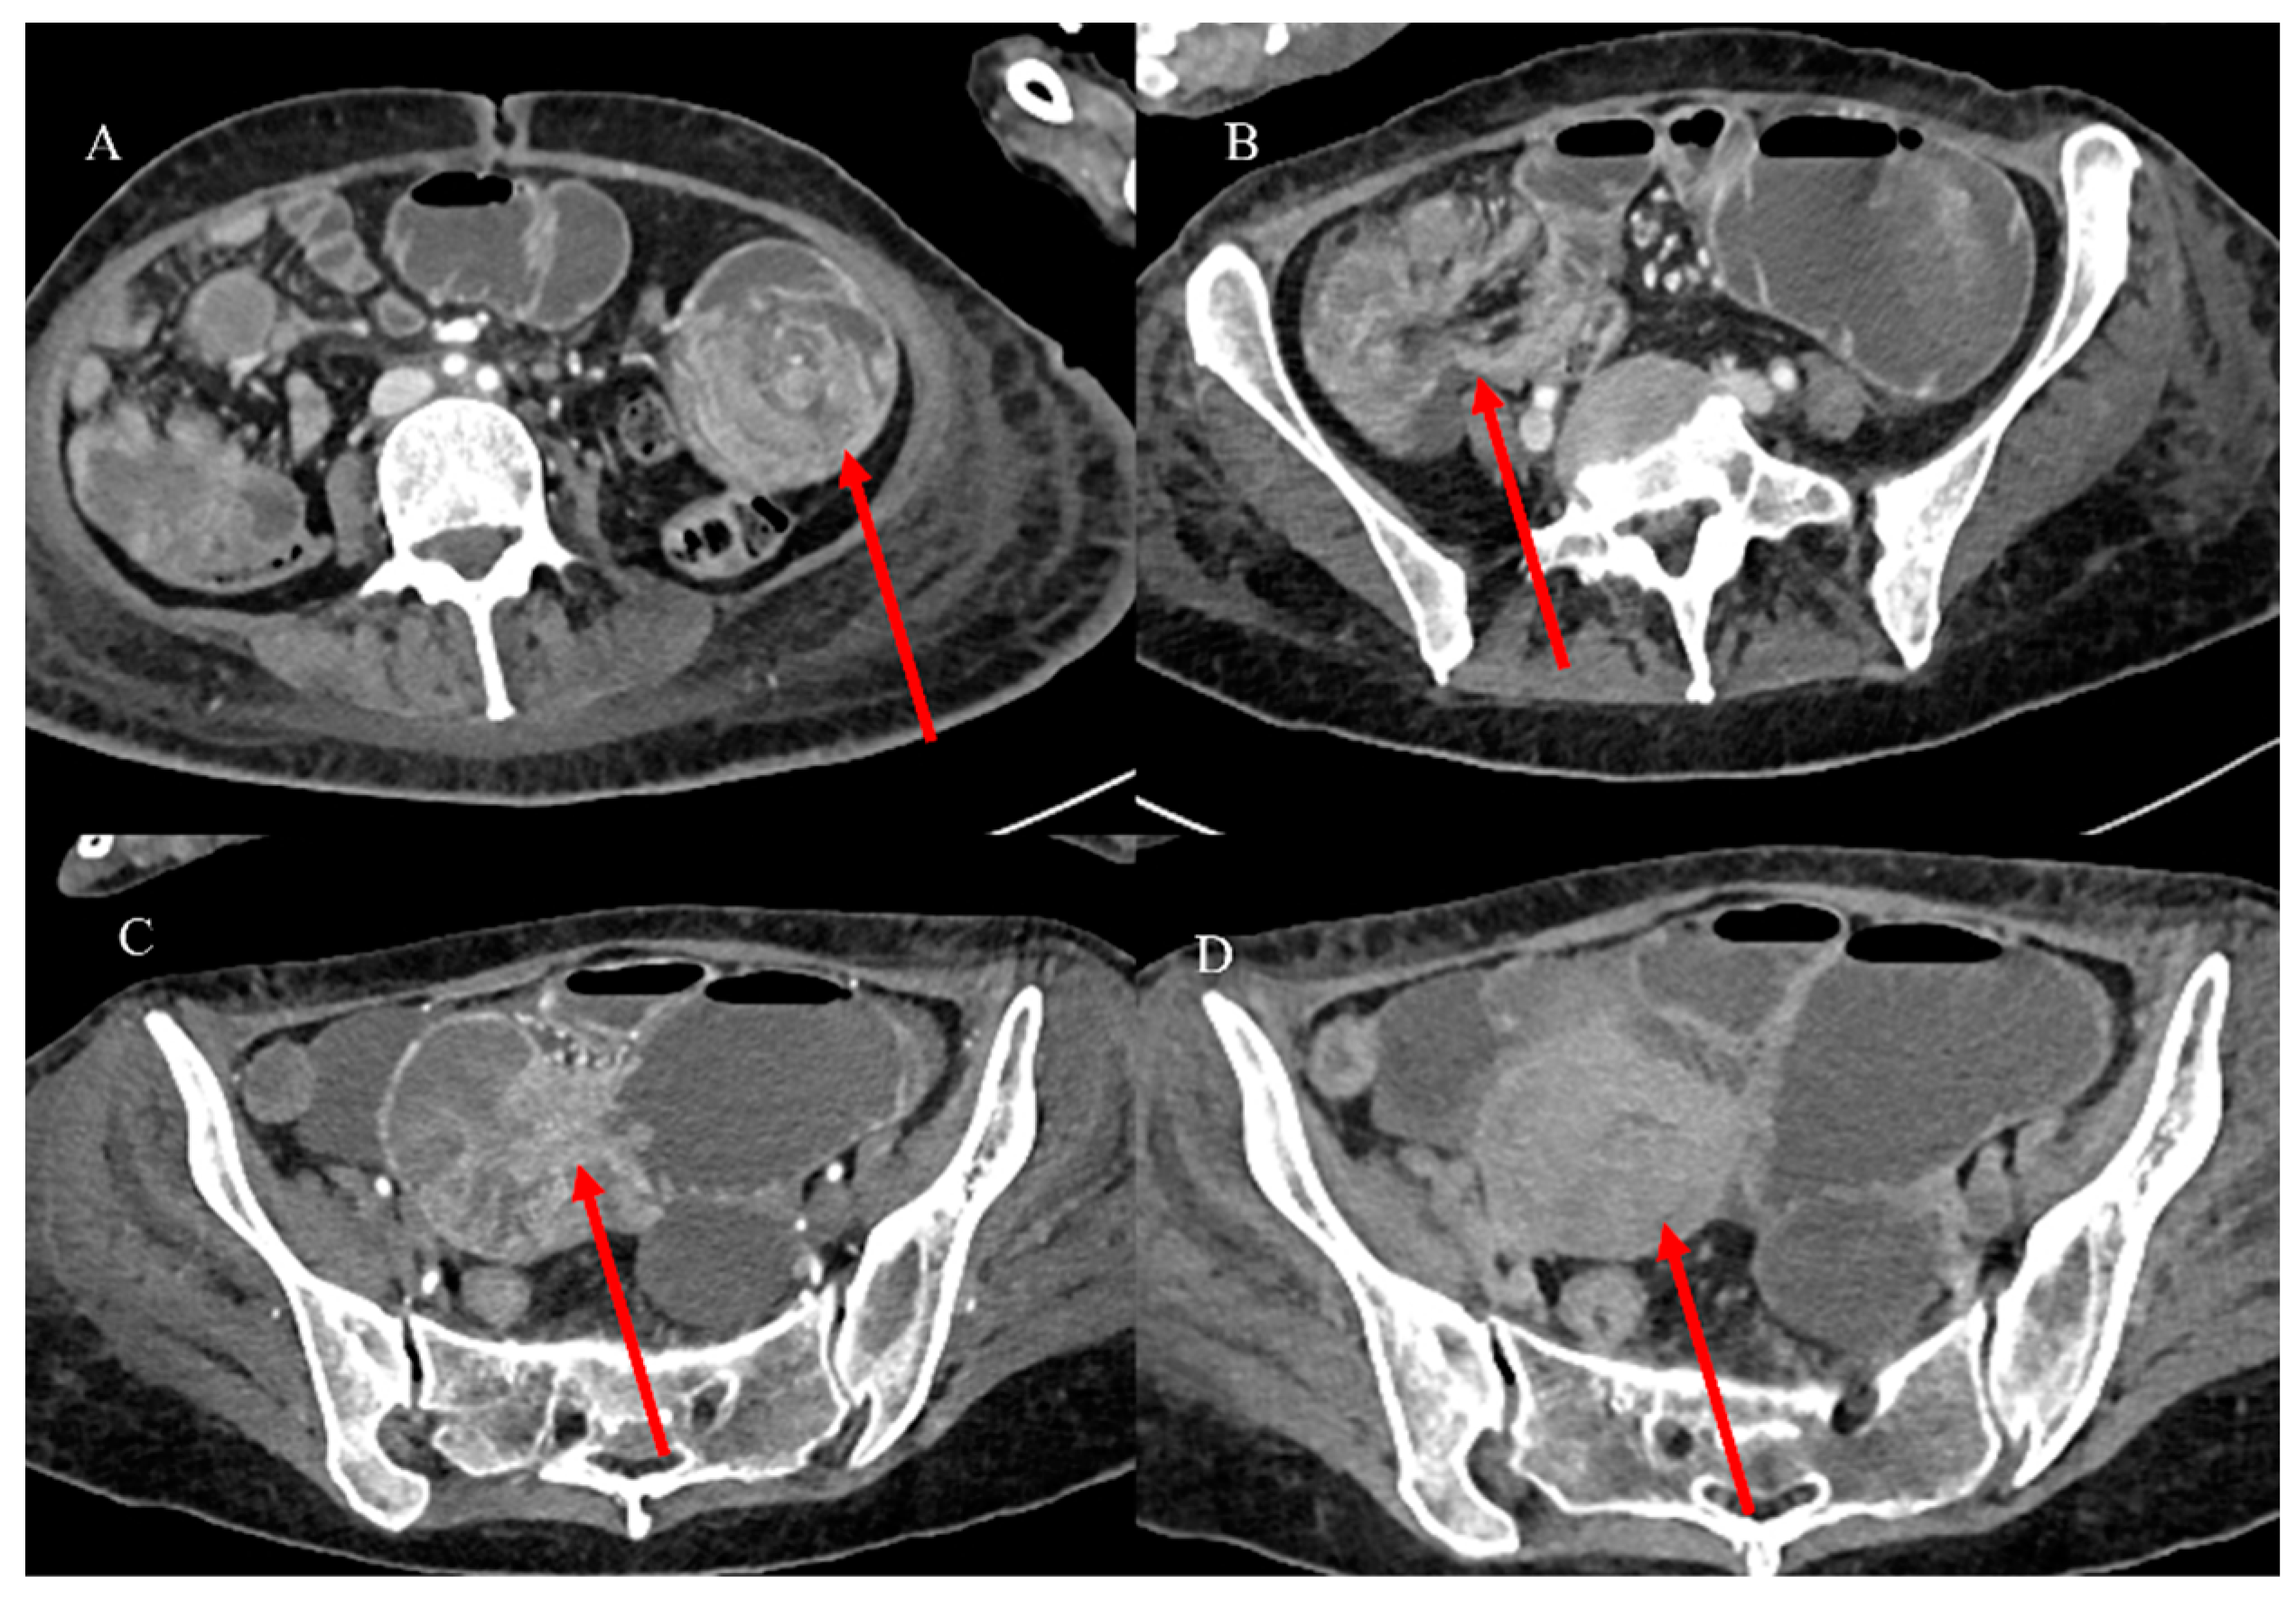

2.7. Metastatic Presentation of Small Bowel Tumors

- Song, Y.; Li, M.; Shan, J.; Ye, X.; Tang, S.; Fang, X.; Ding, K.; Yuan, Y. Acute small bowel obstruction: A rare initial presentation for the metastasis of the large-cell carcinoma of the lung. World J. Surg. Oncol. 2012, 10, 26. [Google Scholar] [CrossRef] [PubMed]

- Alsobahi, N.A.; Mohammed, T.A. Small bowel obstruction as first presentation of metastatic lobular breast cancer for pilgrim patient. Int. J. Surg. Case Rep. 2024, 120, 109855. [Google Scholar] [CrossRef]

- Naoshima, K.; Abe, K.; Murakami, K.; Takaya, K.; Nakano, T. Small Bowel Obstruction Caused by Small Intestinal Metastasis Secondary to Esophageal Carcinoma. Case Rep. Surg. 2021, 2021, 9728424. [Google Scholar] [CrossRef] [PubMed]

- Sparkman, B.K.; Pearce, J.; Klein, K.; Idowu, M.; Askari, K.; Fernandez, L.J.; Trevino, J.G.; Sullivan, S.A.; Miller, D.T.; Randall, L.M. Metastatic Uterine Leiomyosarcoma presenting as small bowel intussusception at two independent visits. Gynecol. Oncol. Rep. 2023, 51, 101306. [Google Scholar] [CrossRef]

- Attiyeh, M.A.; Malhotra, G.K.; Li, D.; Manoukian, S.B.; Motarjem, P.M.; Singh, G. Defining MRI Superiority over CT for Colorectal and Neuroendocrine Liver Metastases. Cancers 2023, 15, 5109. [Google Scholar] [CrossRef]

- Shenoy-Bhangle, A.; Baliyan, V.; Kordbacheh, H.; Guimaraes, A.R.; Kambadakone, A. Diffusion weighted magnetic resonance imaging of liver: Principles, clinical applications and recent updates. World J. Hepatol. 2017, 9, 1081. [Google Scholar] [CrossRef]